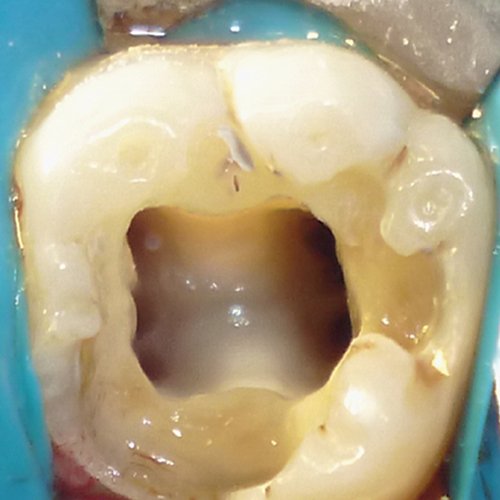

Conozca más casos dentales en nuestra Fanpage: ABC Clinica Dental dentista en guatemala. Implantes dentales